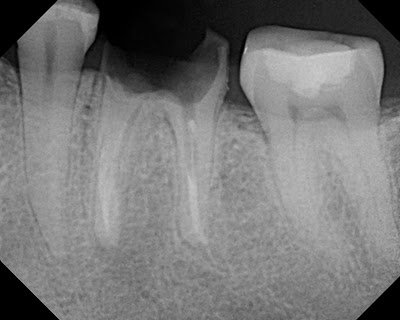

This pt presented in 2006 with an prior rct & acute apical abscess. Retx was recommended. A periapical lesion is noted on the distal root.

Retreatment completed in 2006.

In 2010, the patient returns with symptoms. The distal lesion has healed, and the mesial margin of the crown shows leakage. It is recommended to remove crown and excavate decay.

The radiographic history would indicate that the endodontic retreatment performed in 2006 was was successful with healing of distal lesion.